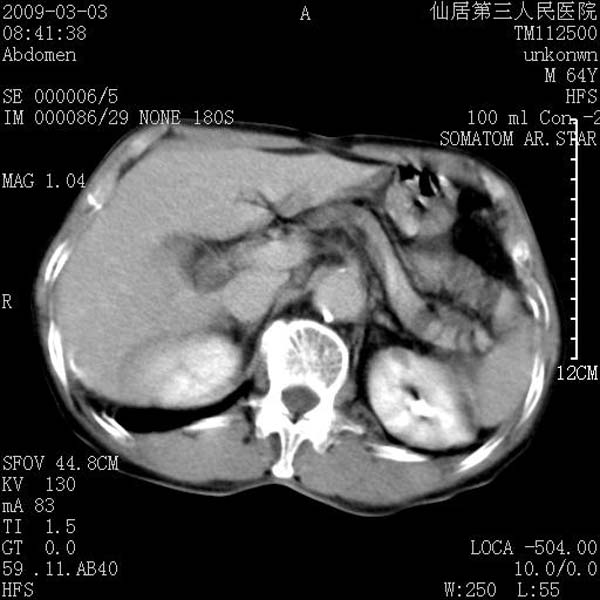

标题: CT18469:男性,64y,体检B超示肝脏低回声肿块,有胃溃疡手术 [打印本页]

标题: CT18469:男性,64y,体检B超示肝脏低回声肿块,有胃溃疡手术

患者,男性,64y,体检b超示肝脏低回声肿块,有胃溃疡手术史。

考虑----胃肠道间质瘤可能性大

从平扫及增强的特点来看,支持肝脏腺瘤并出血。

考虑胃间质瘤可能性大。

胃肠道间质瘤!

ct值呢?感觉没强化,象囊性。

考虑肝静脉韧带裂区良性占位性病变(囊肿?)。

考虑肝囊肿并出血可能性大.

考虑高密度囊肿可能性大